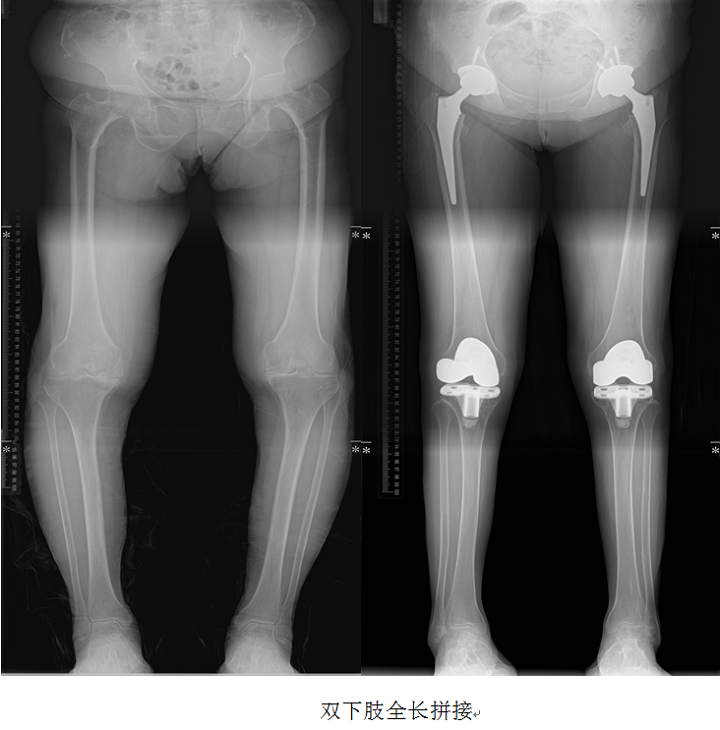

下肢全長(zhǎng)拼接:

從髖關(guān)節(jié)到踝關(guān)節(jié),采用3-4次分段曝光法采集信息,既可以全面觀察骨與關(guān)節(jié)的形態(tài)、密度的改變,又可對(duì)生理角度(如髁-髖角、脛股機(jī)械軸夾角、平臺(tái)-踝角等)、應(yīng)力線等各種角度、徑線進(jìn)行測(cè)量。負(fù)重軸線的改變會(huì)使關(guān)節(jié)負(fù)荷分配線發(fā)生變化,影響關(guān)節(jié)負(fù)荷傳導(dǎo)。如發(fā)生在膝關(guān)節(jié)會(huì)造成一側(cè)關(guān)節(jié)軟骨承受過(guò)大應(yīng)力,導(dǎo)致軟骨的逐漸磨損,引起膝關(guān)節(jié)炎。